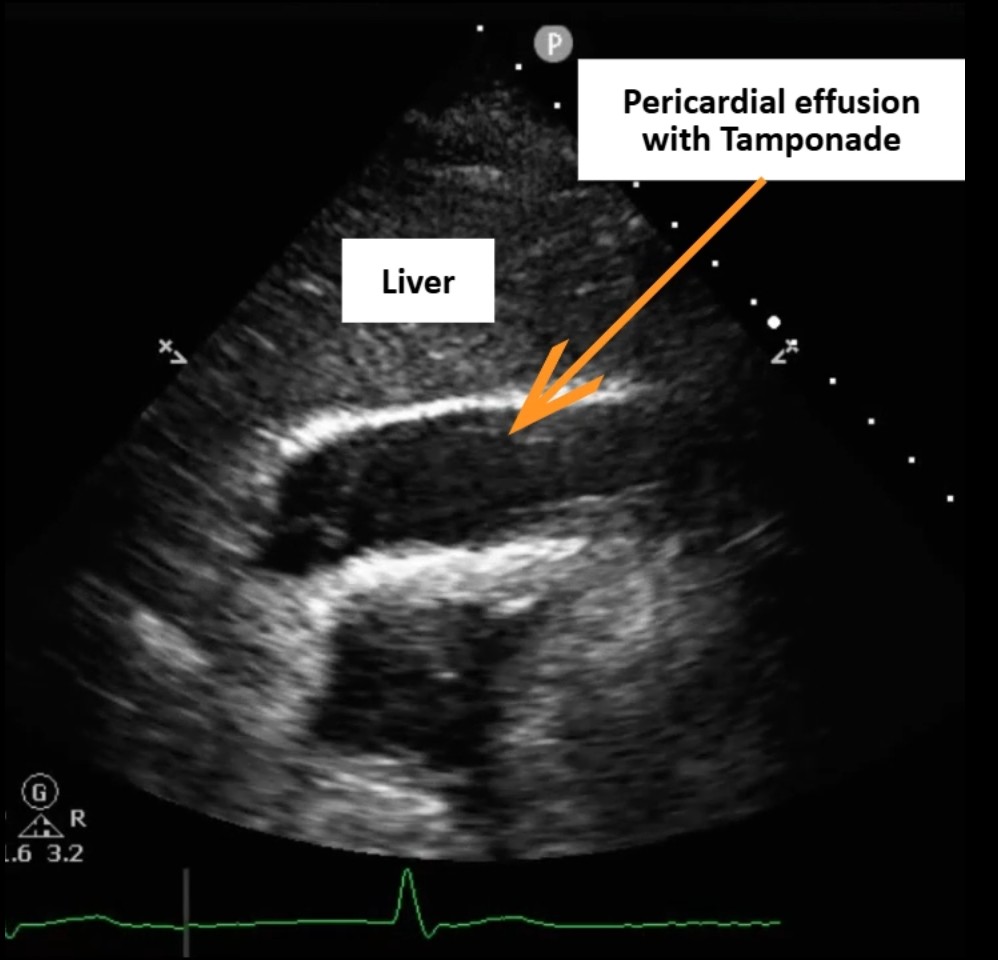

Arterial blood gas showed no CO©ü retention or hypoxemia, and hemogram revealed no anemia. Serial cardiac enzymes demonstrated a declining trend of Troponin I (12.5¡æ7.9 ng/mL), suggesting no ongoing ischemic progression. Bedside echogram revealed a 1-cm circumferential pericardial effusion with right ventricular diastolic collapse, consistent with cardiac tamponade, but pericardiocentesis was not feasible due to the absence of a safe window. Computed tomography excluded aortic dissection.

Review of the primary PCI angiography revealed no contrast extravasation; however, the Sion wire had advanced deeply into a small distal branch of the LCx artery, in hindsight possibly causing a distal micro-perforation. Repeat angiography demonstrated patent stents in both the left circumflex and obtuse marginal branches without in-stent thrombosis. No persistent or visible extravasation was noted, suggesting spontaneous hemostasis of the suspected micro-perforation.

Due to cardiac tamponade with progressing shock, the patient was immediately evaluated for emergency intervention. A cardiovascular surgeon performed an emergent subxiphoid pericardiotomy under local anesthesia. After sterile preparation, a linear incision was made over the xiphoid region and deepened to the pericardium, which was opened bluntly. Approximately 450 mL of fresh blood was evacuated, and a 28 Fr chest tube was inserted for continuous drainage. The patient¡¯s blood pressure rose dramatically from 70 mmHg systolic to over 200 mmHg after decompression, indicating effective relief of tamponade. Once hemodynamic stability was achieved, the interventional cardiology team performed repeat coronary angiography to identify the potential source of bleeding, as detailed in the previous section. The patient was then transferred to the intensive care unit for close monitoring. Chest tube drainage was minimal (0 mL) on postoperative day 2, and follow-up bedside echocardiography revealed no residual pericardial effusion or right ventricular diastolic collapse. The chest tube was subsequently removed, and the patient was transferred back to the general ward for discharge preparation.